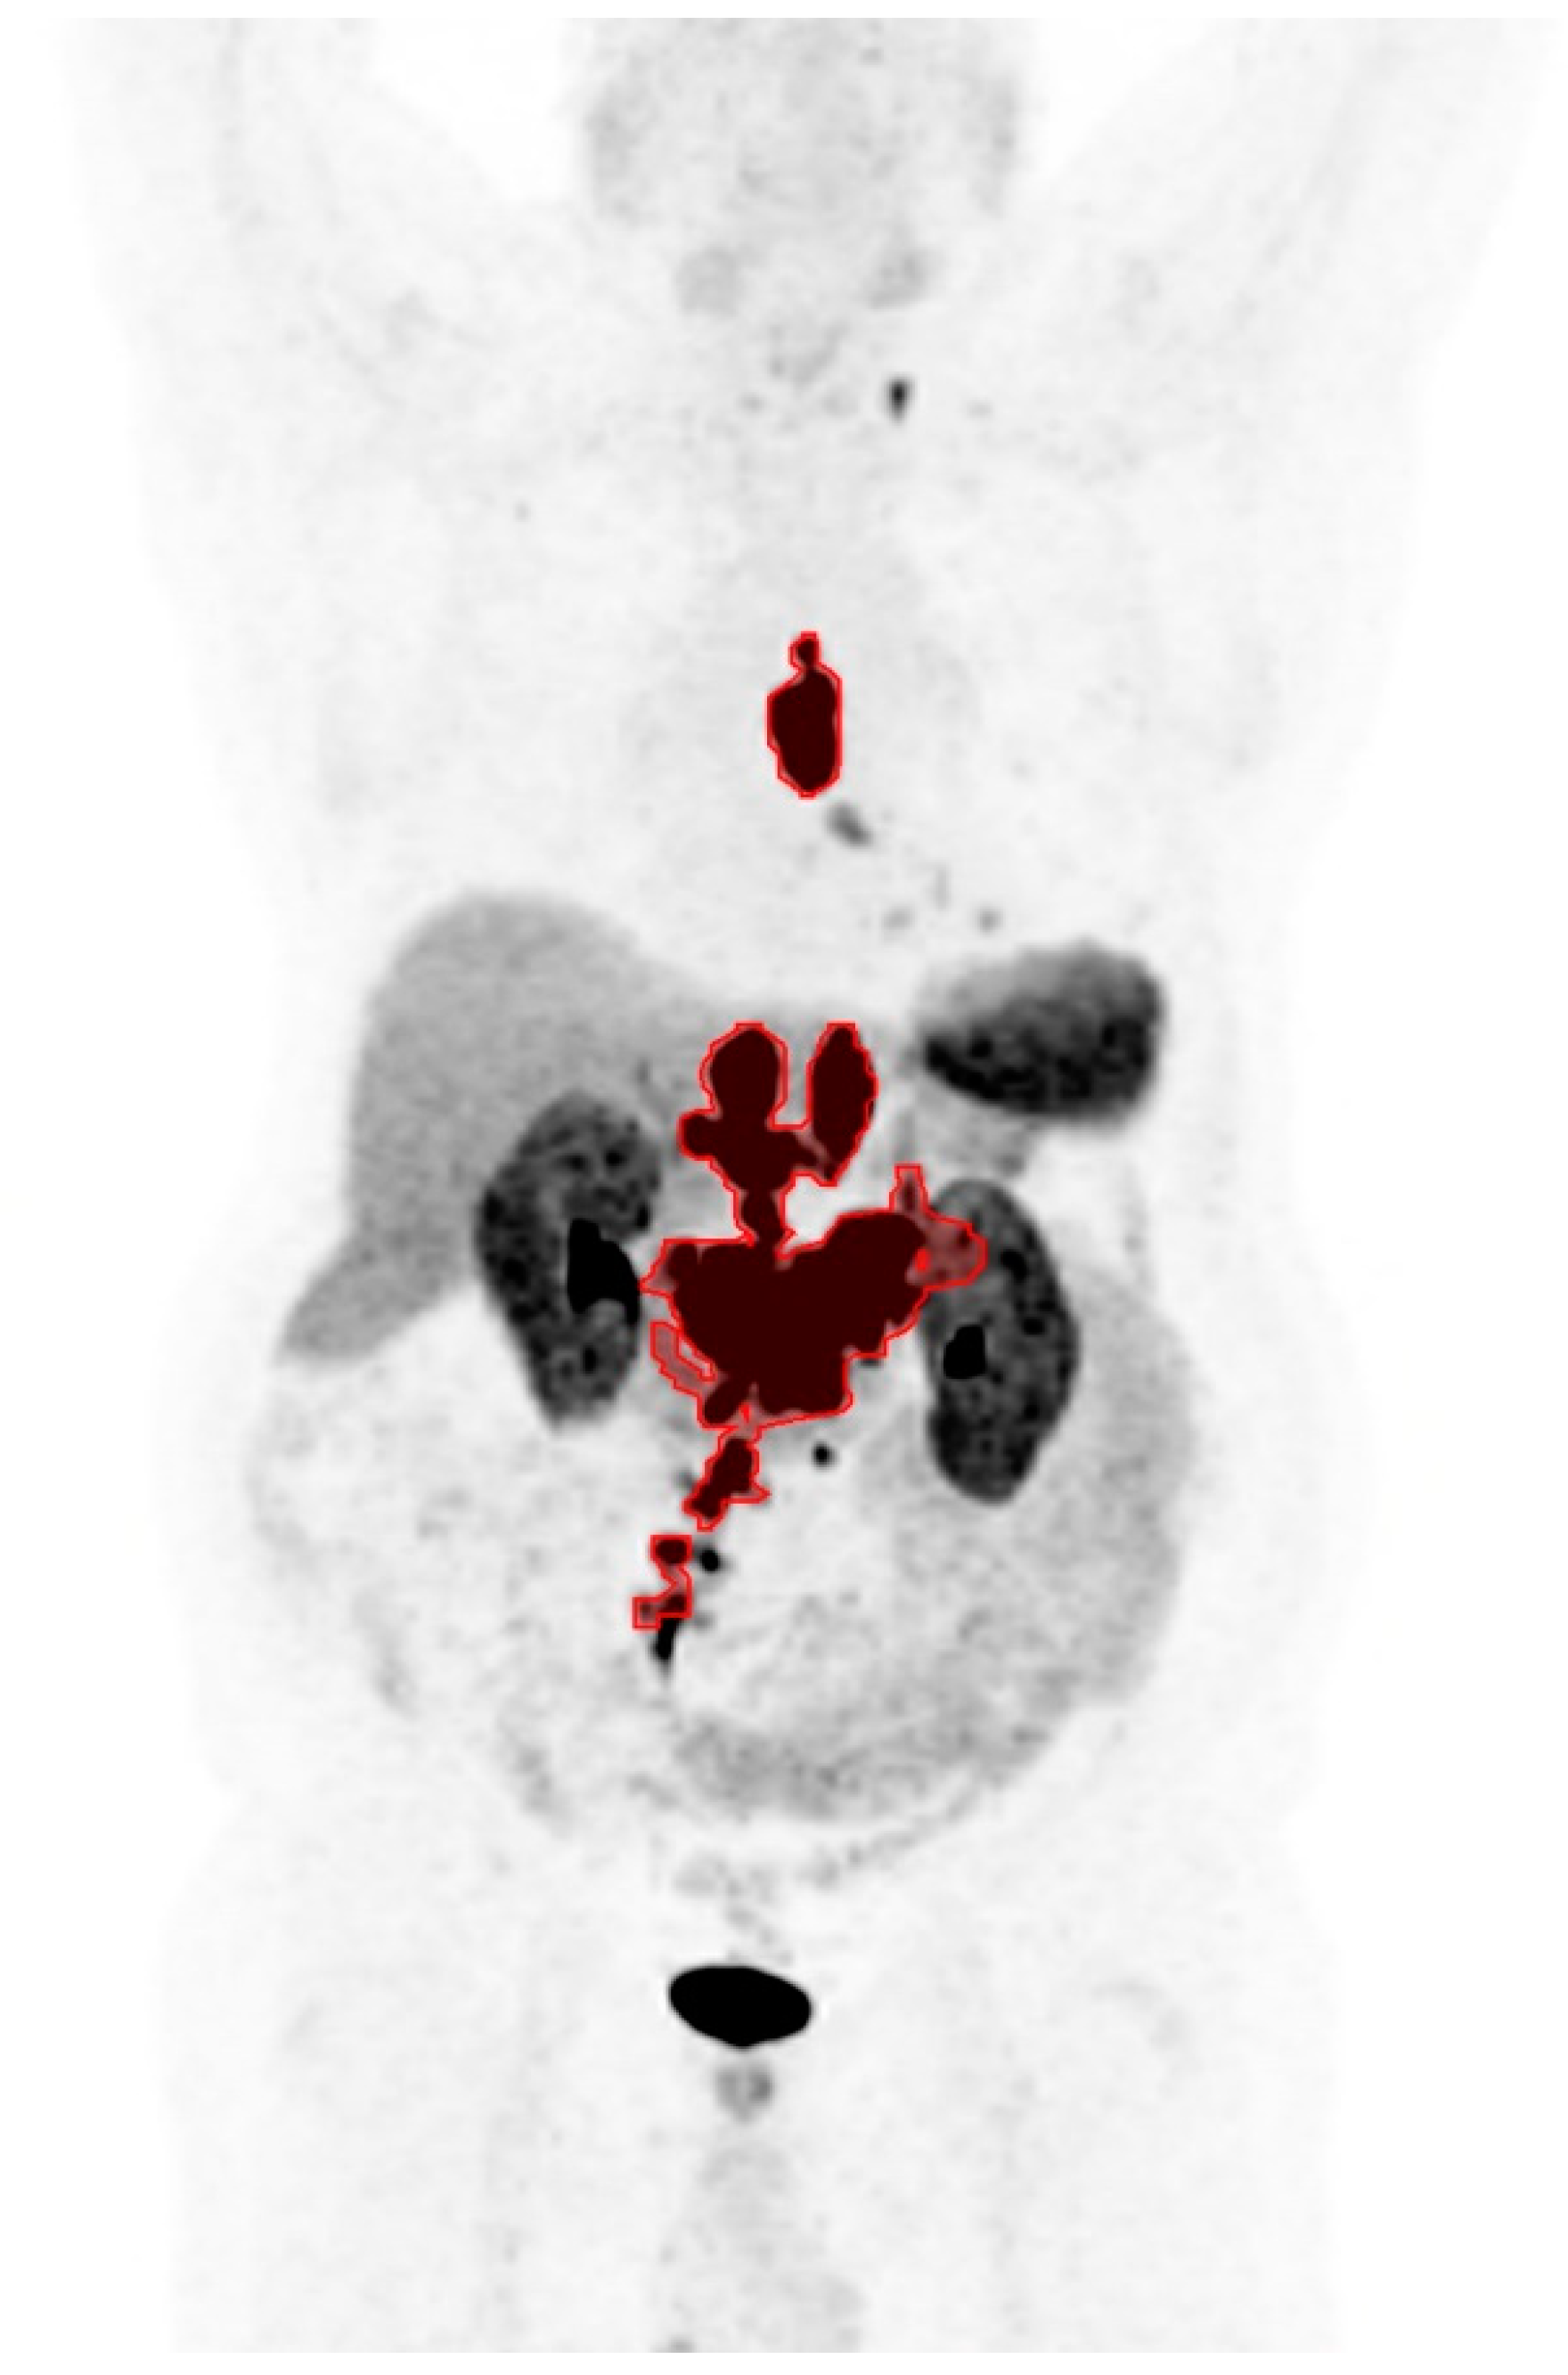

Prediction of 177Lu-DOTATATE Therapy Outcomes in Neuroendocrine Tumor Patients Using Semi-Automatic Tumor Delineation on 68Ga-DOTATATE PET/CT

3.2. Imaging Parameters